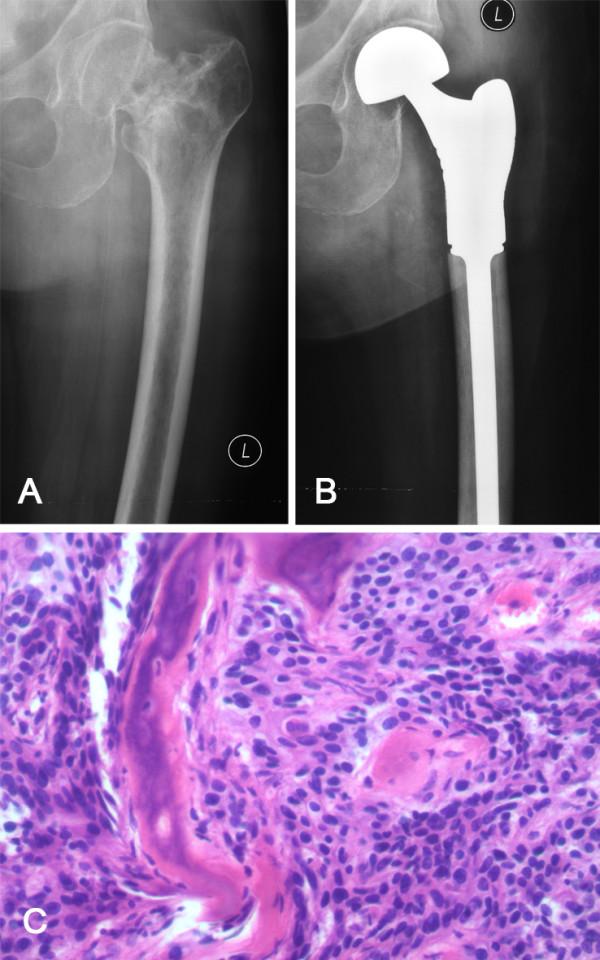

The evaluation, counseling, and management of gynecologic patients with bone metastasis remain a challenge for clinicians. In order to critically evaluate the role of surgery, we retrospectively analyzed the records of 18 patients surgically treated for metastatic gynecologic tumors of bone, focusing on quality of life, local tumor control, and survival.

Eighteen patients underwent surgical procedures for the treatment of bone metastases secondary to gynecologic cancer between September 2003 and April 2012. The primary cancer sites included the uterus (n = 10), the cervix (n = 5), and an ovary (n = 3). Patients were followed for an average period of 13.8 months (range, 2 to 34 months). A visual analog pain scale (VAS) and Eastern Cooperative Oncology Group (ECOG) performance status were evaluated both pre- and postoperatively.

The median survival time following diagnosis of bone metastasis was 10.0 months. The mean VAS score was 5.8 preoperatively compared with 2.1, 3 months after surgery. The mean pre and postoperative ECOG performance status grades were 3.1 and 2.3, respectively.

The prognosis of gynecological cancer patients with bone metastasis is poor. Some patients had improvement in their quality of life after surgical intervention for bone metastases; however, novel integrated treatment modalities should be investigated.